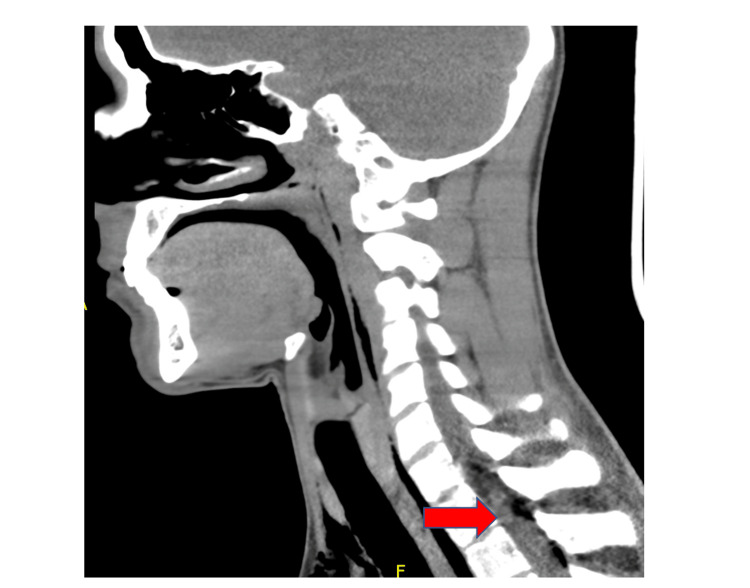

A chest x-ray revealed PM that was well seen on chest CT, and PR was seen in the neck CT (Figures 1, 2). No other findings were seen on abdominal CT. An esophageal swallowing test did not reveal any leakage. Patient was treated conservatively and given capsaicin topical cream and promethazine as needed for nausea and vomiting. Three days later, the chest x-ray did not reveal the PM; he was discharged to the care of his primary care provider (PCP) with advice to discontinue MJ. It is unclear at this time whether the patient had followed up with his PCP after discharge. It was felt that he may have had a microesophageal perforation without any significant extra-luminal damage or rupture of a peripheral bleb causing the PM and PR.

CHS has been linked to numerous cases of AKI and three suspected deaths [ref. 6]. Additionally, only two other cases of otherwise spontaneous PM in association with CHS have been reported [ref. 7]. The mechanism of PM seems likely to be a micro-tear in the esophagus that thus far has not been reported to cause Boerhaave syndrome which requires anything beyond observation. Another theory proposed to explain the association of spontaneous PM, and hyperemesis syndrome, includes the increase in thoracic pressure caused by Valsalva maneuvers during vomiting which in turn predisposes an individual to barotrauma that can rupture bullae/blebs [ref. 8]. This association of MJ smoking leading to bullae ruptures potentially causing PM and pneumothorax is more likely to be seen with concomitant tobacco smoking [ref. 9,ref. 10]. Likewise, we believe PR is another potential complication of CHS. Although located in the spinal canal, it has not been reported in association with CHS, but it has been seen in up to 9.5% of cases with PM and often presents with few symptoms specific to the diagnosis [ref. 11]. No known cases of PR have been reported with CHS. Although PR and PM are uncommonly reported with CHS, it can be seen in other conditions that cause severe vomiting through the mechanisms mentioned above.